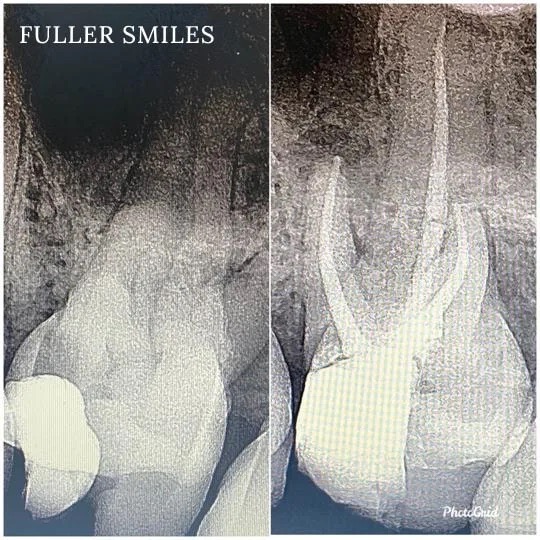

A thorough clinical exam, endodontic screening and proper x rays led to the diagnosis of irreversible pulpitis(inflamed pulp tissue) due to secondary dental caries with inflamed periodontal ligaments.

Our Dentists used the latest technology and highest quality products to finish this beautiful root canal followed by a post and core to give the tooth additional strength. The tooth was crowned after the root canal to restore function and aesthetics.